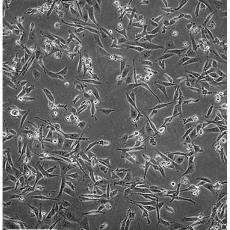

MDA-MB-231

中文名稱 人乳腺癌細胞

組織來源 乳腺腺癌;胸腔積液轉移;女性

生長特性 adherent

形態特征 epithelial

細胞描述 MDA-MB-231來自患有轉移乳腺腺癌的51歲女病人的胸水。在裸鼠和ALS處理的BALB/c小鼠中,它能形成低分化腺癌(III級)。